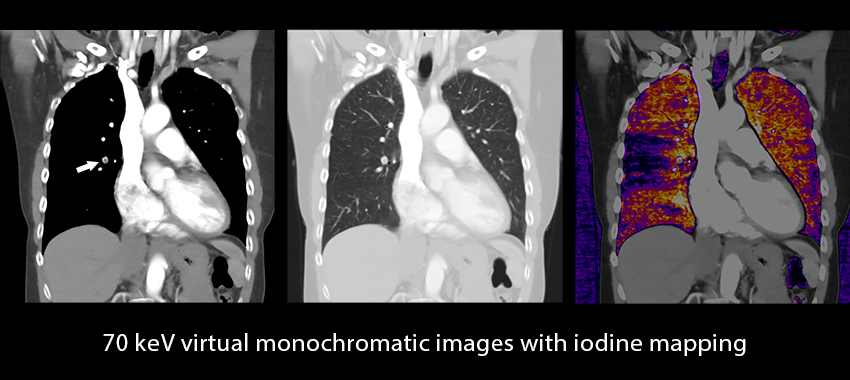

DEEP LEARNING SPECTRAL

A fully integrated end-to-end spectral workflow

The Aquilion ONE / PRISM Edition harnesses the temporal benefits of rapid kV switching with patient specific mA modulation and combines them with a Deep Learning reconstruction that delivers excellent energy separation and low-noise properties.